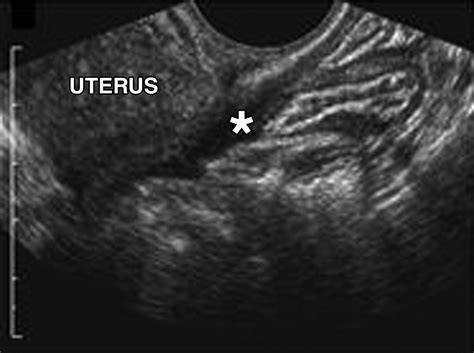

The Posterior Cul De Sac is a small, pouch-like structure found at the end of the rectum. It is part of the larger cul-de-sac system, which includes the anterior and lateral cul-de-sacs. The posterior cul-de-sac is particularly important because it is the lowest point in the pelvic cavity, making it a critical area for the accumulation of fluids and waste materials.

Anatomically, the Posterior Cul De Sac is situated between the rectum and the anal canal. It is lined with mucous membranes that secrete mucus, which helps to lubricate the rectum and facilitate the passage of stool. This mucus also plays a role in protecting the rectal lining from irritation and infection.

• posterior cul de sac fluid